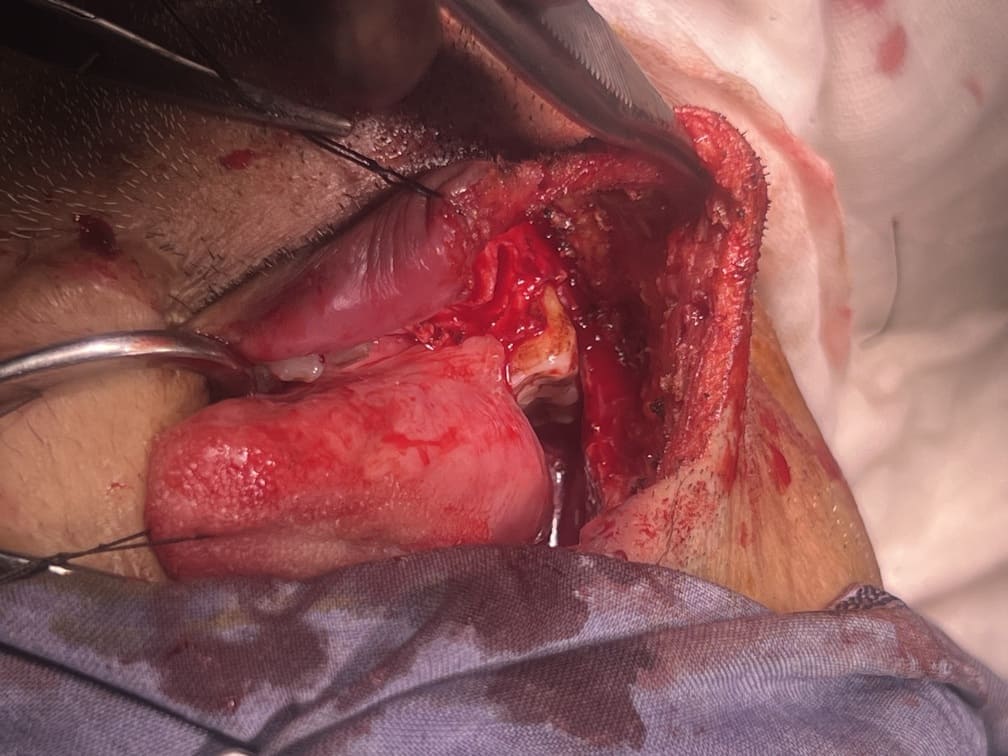

57 years old female suffering from left buccal mucosa growth involving left RNT and gingival surface of lip extending up to right angle mouth.left modified neck dissection with left distal segmental mandibulectomy with wide excision of left buccal mucosa with left RMT growth with excision gingival margin of lower lip with left pectoralis with right nasolabial flape done.

29-12-2025